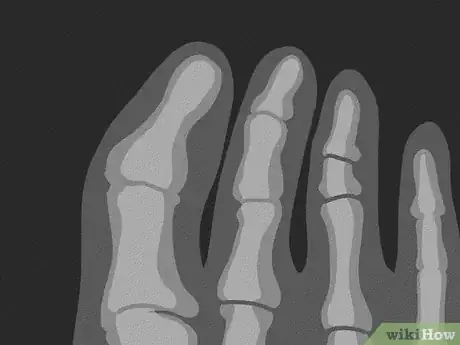

6Go for an x-ray if your toe is immobile or looks crooked. Many injuries that cause nail avulsion can also cause broken bones. Check your injured toe to see if it bends and straightens all the way. If not, or if it’s sticking out at an odd angle, it’s worth checking to see if it’s broken. Get emergency care for an x-ray and proper treatment.[18]

- Broken toes typically heal well on their own, as long as you splint them.